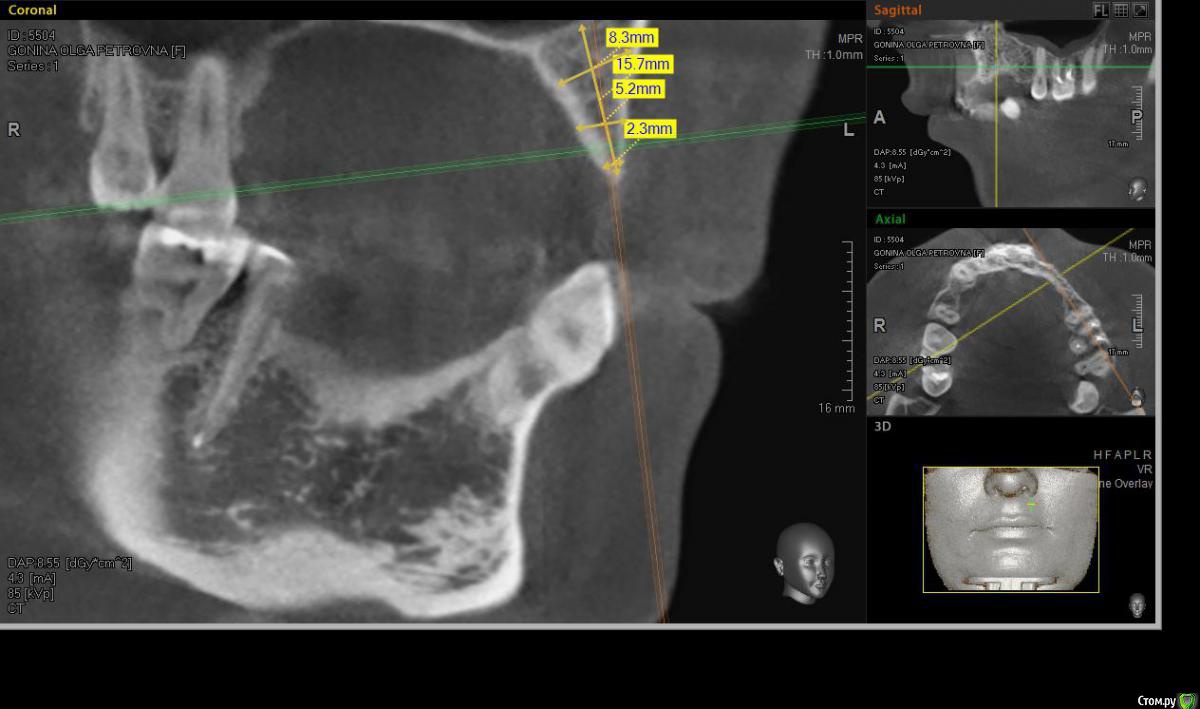

denis1987 Опубликовано 6 декабря, 2014 Поделиться Опубликовано 6 декабря, 2014 Здравствуйте, коллеги. У пациентки частичная вторичная адентия на верхней челюсти слева, отсутствующие зубы 22,23,24. С ортопедом запланировали имплантацию. Снимки прилагаю. Форма альвеолярного гребня вроде как то не особо располагает для расщепления, но все таки хочу попробовать. За ответы заранее спасибо. Ссылка на комментарий